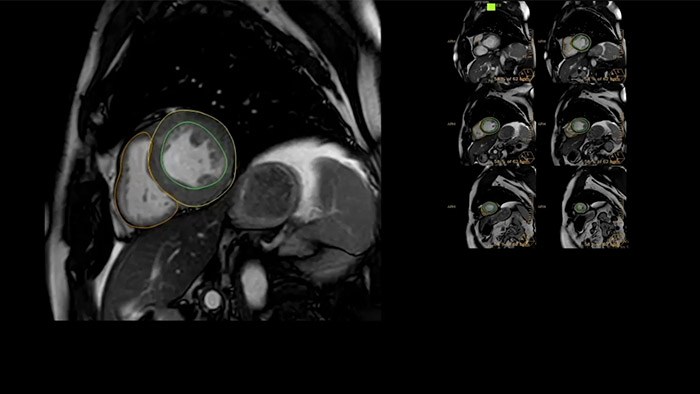

IntelliSpace Portal offre Comprehensive Cardiac RM Suite che fornisce flussi di lavoro dedicati per analisi funzionale, vitalità del miocardio, LGE, valutazione della mappatura cardiaca e analisi funzionale dei ventricoli destro e sinistro in meno di 5 minuti per caso1.

IntelliSpace Portal MR CaaS5,6 Strain7 supporta nella diagnosi e nel monitoraggio dei pazienti fornendo parametri globali di strain, quali strain longitudinale globale (GLS), strain circonferenziale globale (GCS) e strain radiale globale (GRS), utilizzando immagini RM in asse corto e lungo e descrivendo inoltre la deformazione del miocardio, come il suo accorciamento, ispessimento e allungamento durante il ciclo cardiaco.